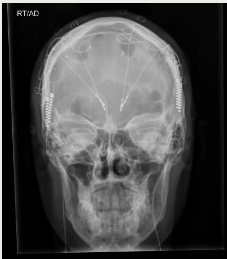

x射線圖像顯示了為治療抑郁癥而植入的兩根DBS電極。

DEPARTMENT OF NEUROSURGERY, BAYLOR COLLEGE OF MEDICINE